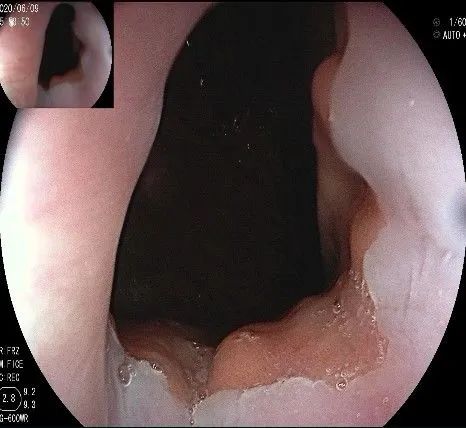

沿切开的边缘,从口侧开始向下进行粘膜下剥离,剥离的间隙是瘤体之上粘膜之下,期间反复进行粘膜下注射。

随着剥离的进行,瘤体与周围组织的关系越来越清晰。

此时瘤体基底部已暴露出来,起源于固有肌层。

这是最后的“根”部。

换用IT刀可以轻松剥离,又避免切入过深造成穿孔。

剥离接近完成,最后连接的薄层组织。